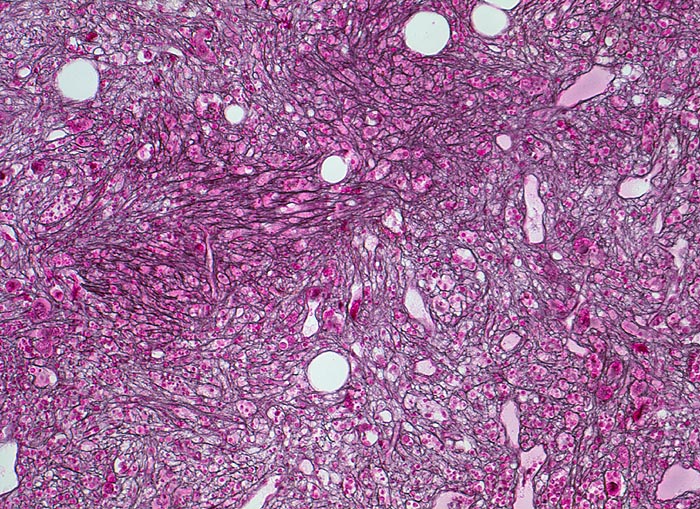

Primäre Myelofibrose (PMF)

Knochenmark, Beckenkamm

Ausgeprägte Reticulinfaservermehrung.

Splenomegalie, leichte Anämie, Leukozytose und Thrombozytose festgestellt bei einer Routineuntersuchung bei abgesehen von leichter Müdigkeit asymptomatischer Patientin.

Im normalen Knochenmark sind meist nur wenige perivaskuläre und peritrabekuläre Fasern nachweisbar. Die Abgrenzung der idiopathischen Myelofibrose von einer essentiellen Thrombozythämie ist im präfibrotischen Frühstadium sehr schwierig. Neben der idiopathischen Myelofibrose kann eine relevante Markfibrose auch bei chronischer myeloischer Leukämie, bei Polyzythämia vera oder sehr selten bei einem myelodysplastischen Syndrom vorkommen.

Histologie

100